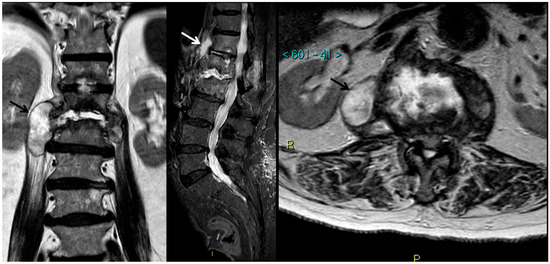

9. Spondylodiscitis

- Jevtic, V. Vertebral infection. Eur. Radiol. 2004, 14 (Suppl. 3), E43–E52. [Google Scholar] [CrossRef]

- Morales, H. Infectious Spondylitis Mimics: Mechanisms of Disease and Imaging Findings. Semin. Ultrasound CT MR 2018, 39, 587–604. [Google Scholar] [CrossRef] [PubMed]

- Stäbler, A.; Reiser, M.F. Imaging of spinal infection. Radiol. Clin. N. Am. 2001, 39, 115–135. [Google Scholar] [CrossRef]

- Maiuri, F.; Iaconetta, G.; Gallicchio, B.; Manto, A.; Briganti, F. Spondylodiscitis. Clinical and magnetic resonance diagnosis. Spine (Phila Pa 1976) 1997, 22, 1741–1746. [Google Scholar] [CrossRef]

- Naselli, N.; Facchini, G.; Lima, G.M.; Evangelisti, G.; Ponti, F.; Miceli, M.; Spinnato, P. MRI in differential diagnosis between tuberculous and pyogenic spondylodiscitis. Eur. Spine J. 2021. [Google Scholar] [CrossRef]